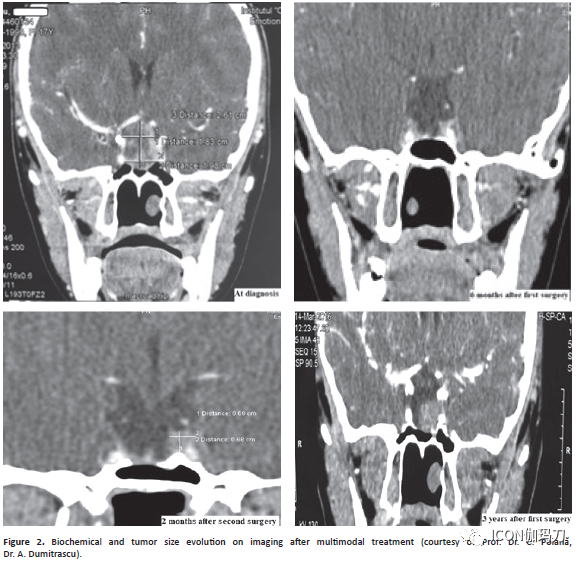

进袭性垂体瘤的多面的行为(versatile behavior)可以被从我们存档的另一个临床病例所强调(图2)。该女性患者,17岁,在初始表现时,有一个30 mm垂体肿瘤,向上扩展和压迫视交叉。她有生长激素分泌过度、促性腺激素和甲状腺激素缺乏的临床症状。在经第二次手术干预后,她接受了垂体经蝶窦手术和伽玛刀放射外科治疗双重治疗,激素没有得到控制。在奥曲肽LAR治疗中加入培维索孟(pegvisomant)后,IGF-1水平才恢复正常。然而,几个月后,病人表现出复视(diplopia)、眼球突出(exophthalmos)、眼睑下垂(palpebral ptosis)和月经自发行经(spontaneous reappearance of mense),可能与卒中有关。

图2多模式治疗后生化改变和在影像学上的肿瘤大小变化。